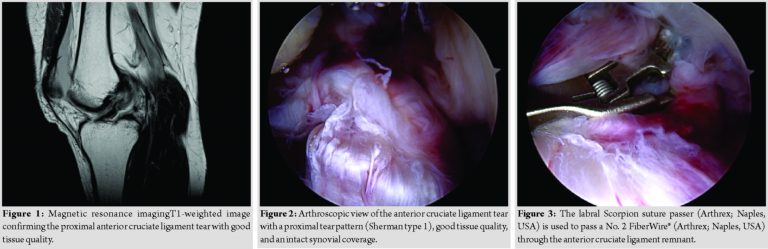

A 47-year-old athletic female patient (165cm; 63kg) was referred to our trauma department by ambulance after she fell twisting her left knee while downhill skiing at high speed. Clinical examination revealed a moderate effusion of the left knee with a positive Lachman, Drawer, and pivot shift test. Radiographic examination showed regular bony configuration of the left knee with no associated fractures while magnetic resonance imaging (MRI) confirmed a proximal ACL tear with no evidence of concomitant chondral/ meniscal/ ligamentous injuries (Fig. 1). The patient underwent a knee arthroscopy on the same day where the radiological findings were confirmed. The ACL tear presented with a proximal tear pattern (Sherman type 1), good tissue quality, and an intact synovial coverage so that an arthroscopic ACL repair using internal brace augmentation was performed (see surgical technique below, Fig. 2, 3, 4). Postoperatively, the left knee was immobilized in a neoprene splint for 2 days only with full weight-bearing as tolerated on crutches for 6 weeks. Passive mobilization of the knee started immediately on the 1stpost-operative day followed by increasing active and assistive mobilization. Knee flexion was limited to 90 degrees for 4 weeks. Physiotherapy (3 times a week) and aquatic therapy (once a week) completed the post-operative care. The patient was discharged in good general condition with a total inpatient stay of 2 days. The 6-week follow-up assessment showed negative Lachman and pivot shift tests, a 1.0mm side-to-side laxity (left side: 6mm, right side 5mm) measured with the KT-1000 arthrometer (MED metric Corp; San Diego, USA) and a restricted knee flexion of 100 degrees while 6-monthfollow-up assessment demonstrated a considerably improved range of movement with 120 degrees of knee flexion. At 1-year follow-up assessment, the pain-and complaint-free patient demonstrated a full range of knee motion and no signs of instability were observed. The patient started with running and cycling exercises 8-week postoperatively and returned to alpine skiing 3 months postoperatively. However, just 1 week after, her 1-year follow-up visit, the patient experienced another severe ski fall with twisting of the left knee and an immediate audible popping noise. A large hemarthrosis developed and patient clinically demonstrated with a positive Lachman, Drawer, and pivot shift test. Consequently, an MRI scan confirmed the diagnosis of a proximal ACL retear (Fig. 5). The patient underwent emergent knee arthroscopy – just 5 h after injury. Intraoperatively, the ACL retear presented with a replicated proximal tearpattern (Sherman type 1), good tissue quality, and an intact synovial coverage so that an arthroscopic ACL re-repair using internal brace augmentation was performed (Fig. 6, 7, 8). Again, the patient was very motivated and compliant with physiotherapy returning to sports 10-week post-injury and alpine skiing 3 months postoperatively. The patient demonstrated a full range of knee motion and negative instability tests with a 1.0mm side-to-side laxity difference (left side: 6mm, right side 5mm) at 6-and 12-month follow-up, respectively. The subjective outcome parameters remained good at 12-month follow-up with the International Knee Documentation Committee score of 83, Lysholm score of 95, and a pre-and post-operative Tegner score of 7. MRI at 12-month follow-up confirmed the integrity of the repaired ACL (Fig. 9).

A hemarthrosis was drained on insertion of the arthroscopic cannula in both cases. Using the two standard anterolateral and anteromedial portals, an arthroscopic washout as well as a diagnostic arthroscopy were performed confirming the radiographically suspected findings with a hook probe. The ACL was carefully assessed, including tear pattern, tissue quality, and synovial coverage of the ACL remnant: Aproximal ACL tear (Sherman Type 1) with good tissue quality and an intact synovial coverage as well as no concomitant osteochondral lesions nor meniscal injuries were present in both arthroscopies (Fig. 2 and 6).

An ACL repair utilizing an internal brace augmentation was performed in both cases as popularized by van der List and DiFelice [5]: Using a labral scorpion suture passer (Arthrex; Naples, USA), a No. 2 Fiber Wire® (Arthrex; Naples, USA) was passed 3 times through the ACL remnant – approximately 1cm distal to the ACL tear (Fig. 3 and 7). The femoral tunnel was drilled in an anatomic manner at the femoral footprint with 130degrees knee flexion using a spade tip drill pin (Arthrex; Naples, USA) and a shuttling loop was subsequently passed through the femoral tunnel. The tibial drilling guide (Smith and Nephew, London, United Kingdom) was then placed at the anterior center of the ACL tibial footprint and the tibial tunnel was drilled through a small skin incision on the anteromedial aspect of the tibia. A shuttling loop was passed through the tibial tunnel. A suture retriever (Arthrex; Naples, USA) was placed through the anteromedial portal retrieving the tibial shuttling loop. The femoral shuttling loop as well as the Fiber Wire® suture were then placed into the tibial shuttling loop and passed through the tibial tunnel. Using the femoral and tibial shuttling loop, the Internal Brace construct consisting of a Tight Rope®(Arthrex; Naples, USA) armed with a Fiber Tape®(Arthrex; Naples, USA) and the Fiber Wire® suture was carefully shuttled through the tibia and femur so that the Tight Rope® button flipped at the femoral cortex (Figs. 4 and 8).